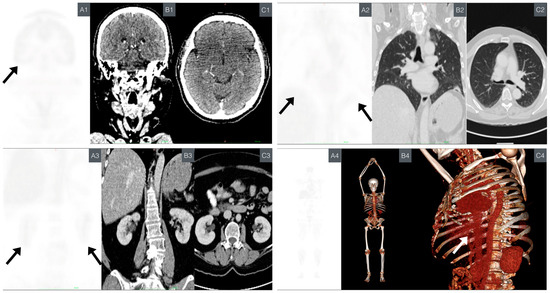

Due to the unavailability of whole-body magnetic resonance imaging (MRI), the preferred imaging modality, PET/CT, was chosen as a screening study for cancer. This decision was made considering its high sensitivity and specificity. Although this imaging modality is still under study due to the use of radiation, it is recommended in LFS screening guidelines because of its significant role in offering benefits in terms of spatial resolution, a major limitation of MRI [69,70,71,72]. Emphasis was placed on areas with higher cancer incidence in LFS patients and particularly those present in direct relatives. These areas were evaluated within standardized uptake value (SUV) ranges of 0.0–1.0 and selected as representative images (Figure 6). More detailed photos, including fusion mode, are provided in Supplementary Figures S1–S4.

Figure 6.

Comparative PET/CT imaging. This highlights the primary organs commonly affected by cancer in patients with LFS. The black arrow on the PET scan indicates the principal organs affected by LFS. PET: displayed on the left (A), showing SUV ranging from 0.0 to 1.0 g/mL. CT: presented in the middle for anatomical reference (B). Axial slide CT (C). (A1–C1) Comparative neuroimaging from SNC. (A1) PET: coronal brain section. (B1) CT: coronal brain section corresponding to the location in image “A”. (C1) CT: axial brain section. (A2–C2) Comparative imaging from the chest. (A2) PET: coronal lung section. (B2) CT: coronal lung section corresponding to the location in image “A”. (C2) CT: axial lung section (A3–C3) Comparative imaging from the abdomen. (A3) PET: coronal kidney section. (B3) CT: coronal kidney section corresponding to the location in the image “A”. (C3) CT: axial kidney section. (A4–C4) Whole-body comparative imaging. (A4) PET: coronal section of the body. (B4) CT: three-dimensional modeling highlighting bone structures. (C4) CT: three-dimensional thoracic modeling focused on the lateral thorax, visualizing the surgical site (white arrow). Abbreviations: central nervous system (CNS), computed tomography (CT), Li–Fraumeni syndrome (LFS), positron emission tomography (PET), standardized uptake value (SUV).

The most significant findings include the following:

- Left rib region increased inflammatory metabolism: metabolic activity was observed in the corresponding area to the resection site with mesh placement. The SUVmax value was 2.8, falling within the expected and favorable prognostic range (<10.2 SUVmax) [73].

- Lung base subsegmental atelectasis: subsegmental atelectasis was noted in lung bases, along with a nodule in the lower lingula. The SUVmax for the nodule was 0.8, which is below the predictive malignancy cutoff value (SUVmax > 2.5) [74].

No evidence of metabolic or morphological abnormalities was found in other organs or structures.